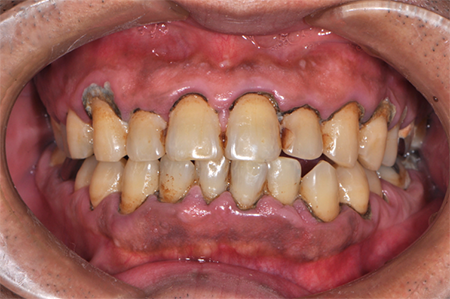

前から見ても歯が欠けてしまい、歯茎も赤く腫れてしまっているのが分かります。

一般的には入れ歯が妥当かと思われますが、患者様は33歳、まだまだ人生は長いです。

奥歯がないと前歯でしか噛めなくなってしまい、残っている前歯もいずれダメになってしまいます。